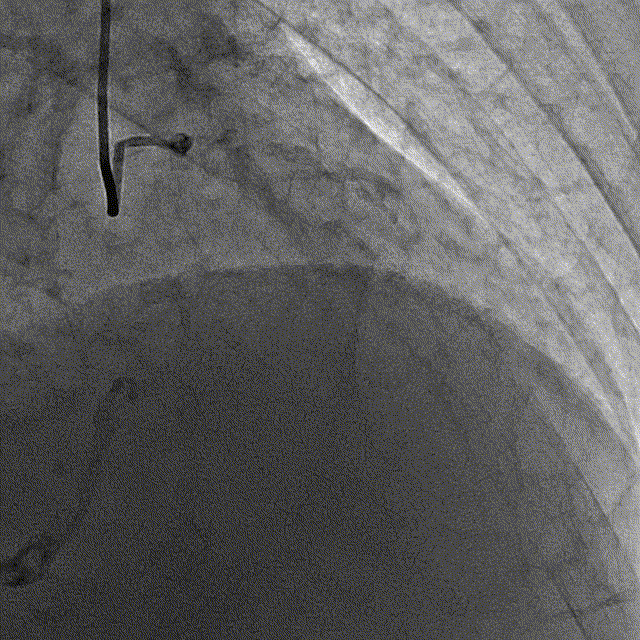

冠脉内介入治疗